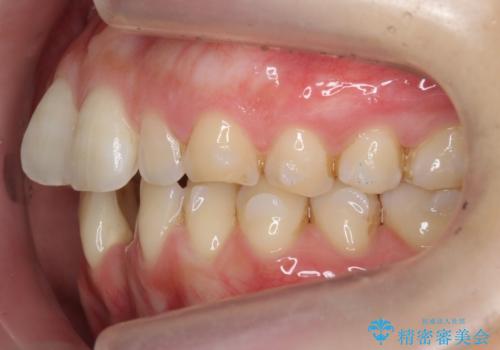

前歯のガタつき インビザラインで 下の前歯を1本抜歯

- 前歯のがたつきを主訴に来院。マウスピース矯正を希望されました。

治療にあたり、下の前歯を一本抜歯しています。

非抜歯で無理に治療をしようとすると、下の前歯の骨が薄く歯ぐきが下がったり、歯がぐらついたり、がたつきが完全にとれないリスクがあることを説明しました。

下の前歯が3本になるため、上下の正中は合わない仕上がりとなりますが、正中を合わせるには上下左右4本抜歯の上、ワイヤー矯正となってしまいます。

それよりは抜歯の数も少なく、メリットが大きいのではないかと説明し、選んでいただきました。

短期間できれいな歯並びになり、大変満足していただきました。